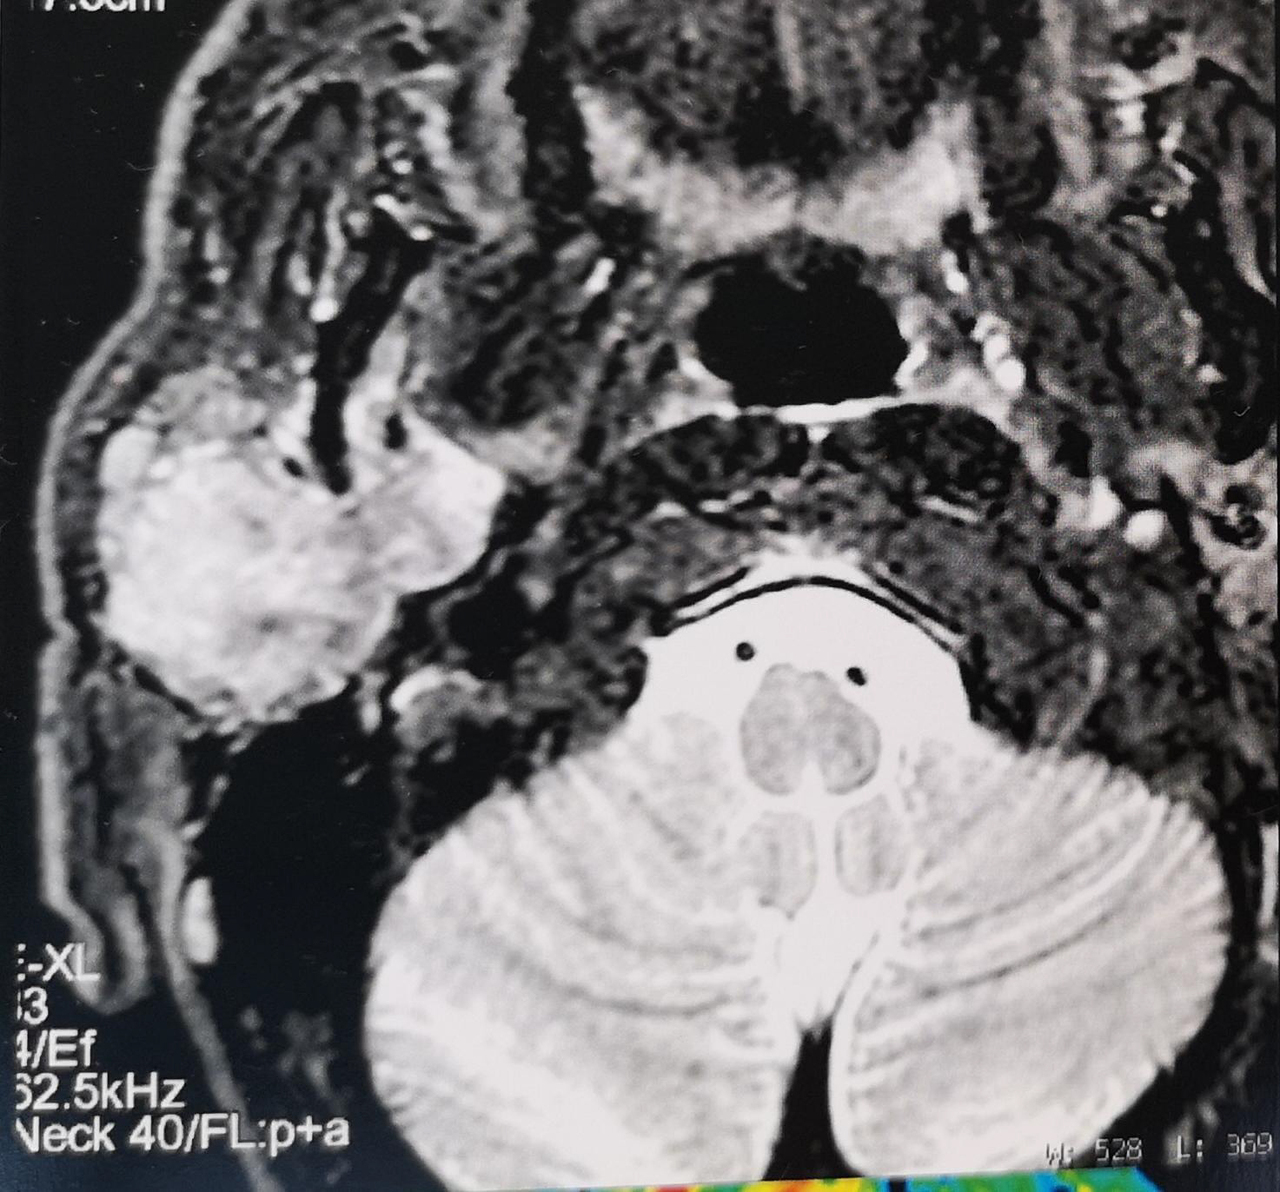

À rechercher devant toute pathologie de la région parotidienne. Un testing musculaire doit être réalisé. Sa présence oriente vers la malignité.

En cas de tumeur maligne, il peut exister des ganglions cervicaux.